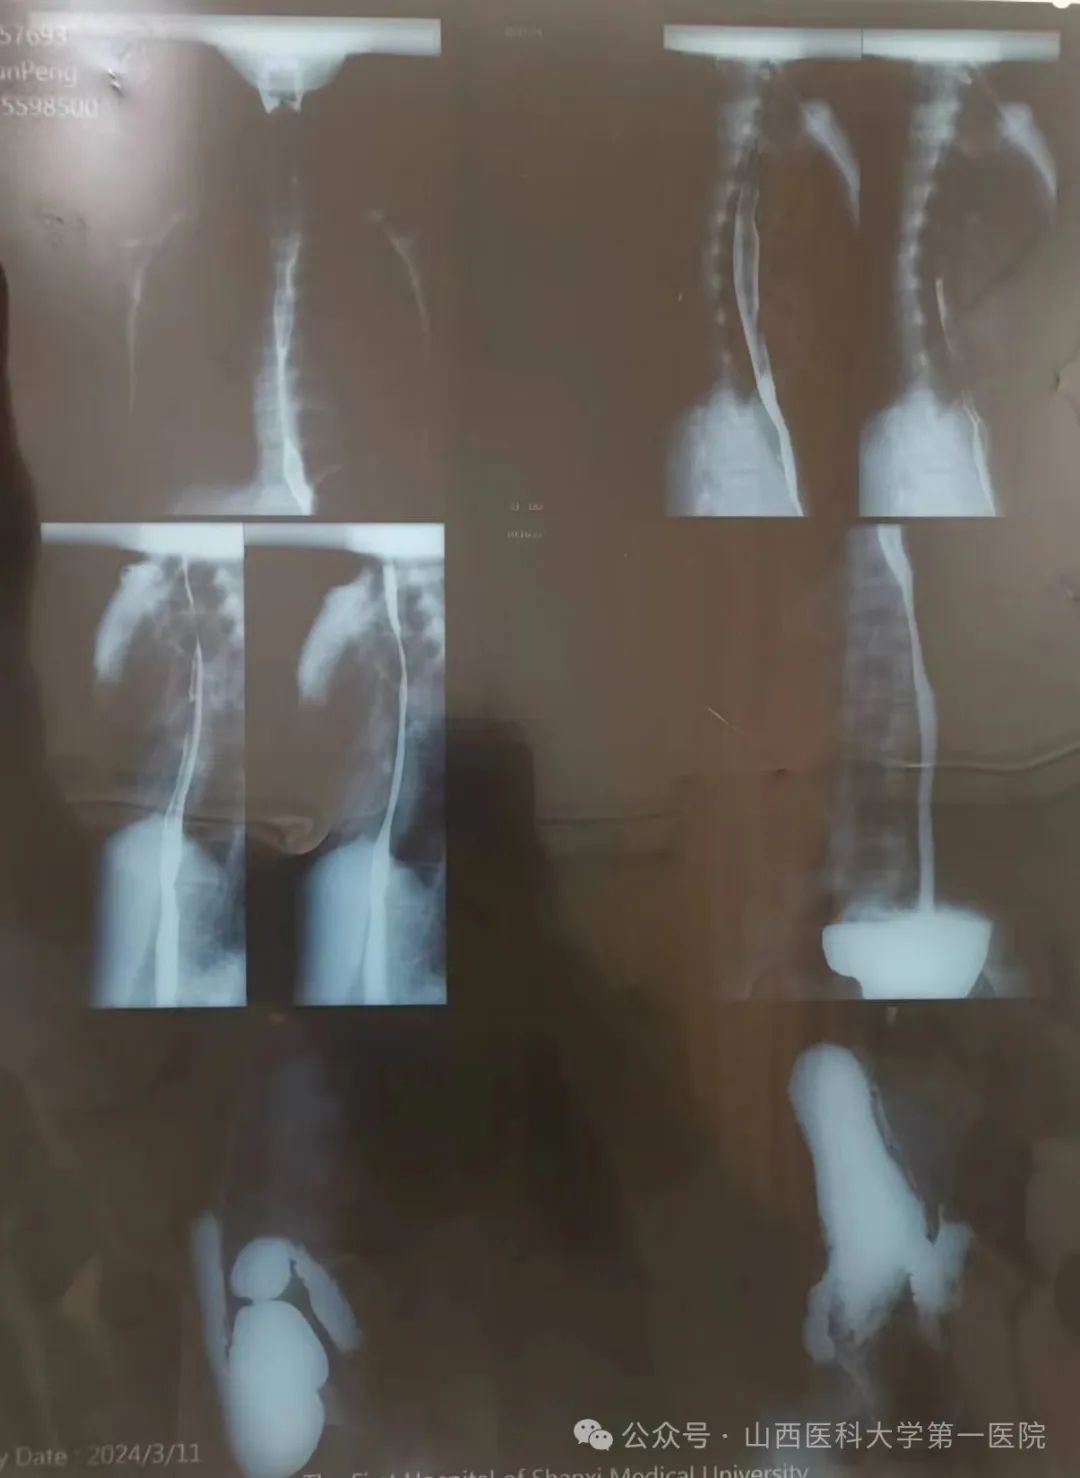

临床营养科接诊一名重度营养不良年轻患者,该患者近两年来无明显诱因反复出现进食后腹胀、腹痛、恶心、纳差,症状进行性加重,进食量逐日减少,检查提示胃下垂及十二指肠淤滞,其带来的进食障碍使体重严重不足,BMI仅12.6kg/m2,肌肉量减少,脂肪流失,合并贫血及闭经,身体的不适导致无法正常生活学习。

门诊完善营养风险筛查、评估、诊断后,孙萍主任医师判断其营养状况已达重度营养不良,死亡风险上升达15%以上,立即为患者联系入住消化内科,由豆张锋、刘婷副主任医师收住入院,留置胃空肠管给予鼻饲营养液,从小剂量、低浓度、低速度起始,逐渐增量增速,并密切观察病情,同时防止再喂养综合症发生。临床营养科主持工作的副主任黄会芳每日带领科室人员为分析病情进展,及时调整营养方案,经过合理有效的肠内营养治疗,目前女孩已顺利出院,并在院外继续进行后续营养治疗。

十二指肠淤滞是由于各种原因引起的十二指肠阻塞,以致十二指肠阻塞部位的近端扩张、食糜壅积而产生的临床综合征,常表现为间歇性进食后腹胀、腹痛、嗳气、恶心、呕吐等。多发生于瘦长体型的中、青年女性,常见病因包括:肠系膜上动脉过长、过短;肠系膜上动脉变异,从腹主动脉分出的部位过低或分出时角度狭窄;异常粗大的静脉横压在十二指肠前方;脊柱前凸畸形使十二指肠占有的空隙减少;瘦长型或内脏下垂者肠管重量牵引肠系膜根部。患者食物摄入不足、体重下降会导致中、重度营养不良的发生,治疗原则需进食无渣食物、少量多餐,餐后采取俯卧位或左侧卧位;如患者进食量加口服肠内营养制剂达不到目标能量的60%,需要置入鼻空肠管,持续滴入营养液,改善营养状况,同时给予消化酶、胃肠动力药等;长期保守治疗无效,影响营养状况或正常工作时,可行手术治疗。